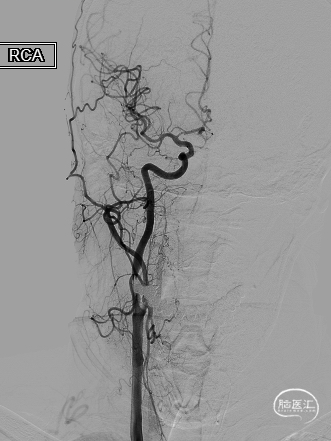

➢ 二期支架置入术

长SIM与6F导引导管同轴,泥鳅导丝引导下将6F导引导管送至颈总动脉远端(左图),保护伞到位(右图)。

4.0*30mm通桥白驹®球囊以6atm扩张(左图箭头),扩张完毕后多角度造影显示狭窄交前明显改善(中图箭头处),扩张完毕后支架置入(右图箭头处)。